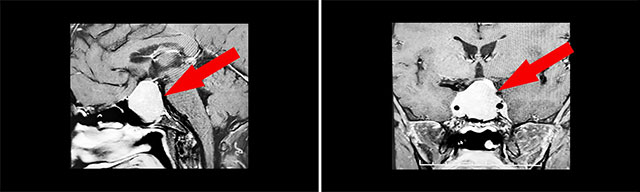

经检查发现:鞍区MRI平扫+增强显示:蝶鞍显著扩大,鞍底下陷,骨质变薄;其内见球形团块状异常信号影,矢橫高径约36×28×31mm,边缘尚青晰、轮廓久光整,向上凸入鞍上池,视交叉受压上抬;双侧海绵窦受累;垂体柄受压、缩短、左侧偏移。

▲ 肿瘤侵袭生长,包绕颈内动脉,knosp分级IV级

针对该患者,唯一的治疗方式就是手术切除肿瘤,减除肿瘤压迫,以期尽早尽力使视力视野恢复。目前手术方式,主要有开颅手术切除肿瘤和经单鼻孔-蝶窦入路切除肿瘤,而患者肿瘤如乒乓球大小,属于垂体大腺瘤,并且侵袭生长,向两侧完全包绕左侧颈内动脉,knosp分级IV级,向上已突破鞍隔压迫视神经、视交叉、下丘脑;向下侵蚀充满蝶窦。